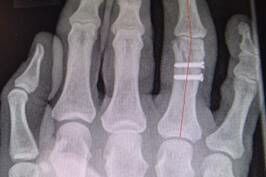

Wegen eines verbliebenen Rotationsfehlers des rechten Ringfingers wurde der Klägerin anderenorts eine Korrekturoperation empfohlen (s. Abb.3

3. In den postoperativen Röntgenkontrollen sei die radiale Abweichung des rechten Ringfingers erkennbar, die einen Drehfehler ohne gesicherten Hinweis nicht ganz ausschließen ließe.

5. Die Fraktur sei in Fehlstellung ausgeheilt. Aus den vorliegenden Dokumenten würde nichthervorgehen, welche weiteren Therapieoptionen diesbezüglich in Anspruch genommen seien.